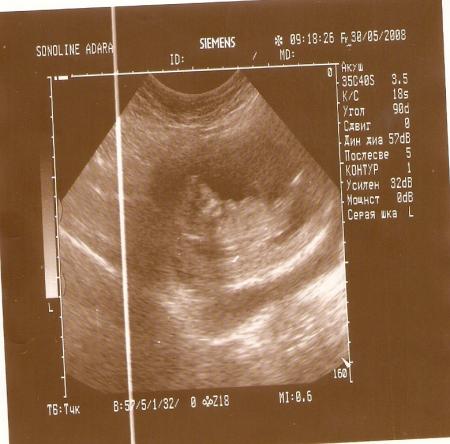

Сделали нам фотографию нашего малыша. Вот делюсь. Тут нам 13 неделек.

Видно конечно не очень хорошо, он просто на спинке лежит. Но если присмотреться, со слева можно разглядеть личико.

Да и у нас тоже особым спокойствием он не отличается. Чтоб фото сделать врач его долго уговаривал.